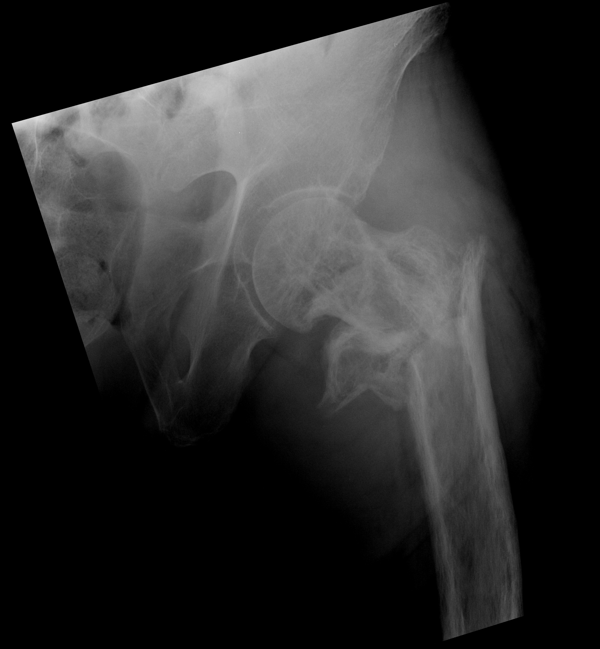

Решающее значение в установлении диагноза перелома шейки бедра имеет рентгенография тазобедренного сустава. У пожилых пациентов приведенные выше симптомы могут проявляться нечетко, а такие заболевания как инсульт или невропатия, вообще, не позволят поставить правильный диагноз без рентгена. Где сделать рентген? Перелом шейки бедра всегда сопровождается сильной болью, поэтому любые лишние движения оборачиваются новыми мучениями, а сопутствующие заболевания внутренних органов усугубляют ситуацию! Решение есть - воспользоваться уникальной услугой – цифровой рентген на дому. К вам приедет врач рентгенолог-травматолог, который выполнит весь комплекс лечебно-диагностических мероприятий и подробно расскажет, что делать дальше.

Получение качественных рентгеновских снимков на дому предъявляет серьёзные требования к рентгеновской аппаратуре. Далеко не каждый переносной рентгенаппарат позволяет получать снимки необходимого качества, чтобы достоверно поставить диагноз. Используемый нами рентгенаппарат АРА 110/160 в комплексе с компьютерным радиографом позволяет получать цифровые рентгеновские снимки высокого качества у пациентов различной комплекции и является уникальной услугой в Санкт-Петербурге, предоставляемой на дому.